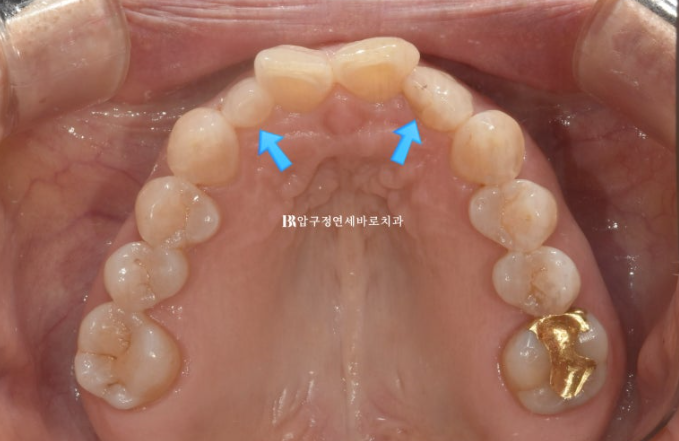

The blue arrow indicates a peg lateral tooth.

On one side, resin had been attached temporarily to fill the gap.

Since orthodontic treatment was planned, the resin used to fill the space was removed, and a scan was taken to make the appliance.

Do you see the space on both sides of the peg lateral tooth?

The intended space for restoring the tooth size was successfully created.